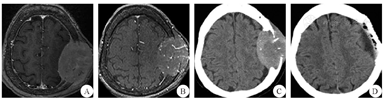

患者1 女性,75岁,因"左顶部头皮下肿物进行性增大8个月余"于2016年4月19日入院。患者在8个月前发现左顶部头皮下无痛性肿物,因肿物逐渐增大而就诊,无头痛、头晕,无恶心、呕吐,无视物模糊,无肢体活动障碍,无抽搐。自起病来,精神食欲可,二便无异常。既往史无特殊。体检:神清,一般情况良好,卡氏功能状况(KPS)评分100分。左顶部头皮下可触及大小约为5.0 cm×7.0 cm类圆形肿物,边界清楚,质地较软,活动度较差、无波动感,局部头皮无红肿热痛、无溃烂。双侧甲状腺不大,未触及明显肿物。神经系统和实验室检查均未见明显异常。胸部CT、心脏、肝胆胰脾、泌尿生殖系彩超均未见明显异常。头颅MRI示:左顶部头皮下硬膜外一类圆形肿块,边界清楚,左侧顶叶受压、中线无明显移位,呈长T1信号,颅骨破坏明显;增强后肿块呈不均匀强化(图1A)。头颅三维飞行时间磁共振血管成像(3D-TOF MRA)示:肿物内部条索状血管影(图1B)。MRA示:肿物血供丰富,以颞浅动脉和脑膜中动脉供血为主。头颅CT示:左顶部头皮下硬膜外一个高密度、边界清楚的肿物,大小约5.1 cm×7.2 cm×6.5 cm,左顶颅骨明显破坏(图1C)。临床诊断:恶性脑膜瘤和颅骨恶性肿瘤可能。于2016年4月22日行左额顶肿瘤切除术,术中见肿瘤位于骨膜内,未侵犯头皮,质地中等,边缘清楚,颅骨破坏明显。在肿瘤边缘外旁开1.5~2.0 cm正常颅骨处切开骨膜,钻孔后铣开颅骨,将骨瓣和肿瘤一起从硬膜上完整剥离。肿瘤血供丰富,源于颞浅动脉、颅骨板障血管、脑膜中动脉,肿瘤基底与硬脑膜粘连紧密、侵及硬膜外层,硬膜内层完整。肿瘤切除后用钛网行一期颅骨成形术。术中出血约350 mL。术后切开肿瘤,见肿瘤呈灰红色、鱼肉状、质地韧。术后CT示肿瘤已完整切除(图1D),骨窗由钛网修复。术后病理结果:HE染色:镜下见肿物大部分由甲状腺滤泡构成,小区域滤泡上皮乳头状增生,细胞核增大,呈毛玻璃样改变;可见异型甲状腺滤泡浸润骨质(图2A)。免疫组化染色:细胞角蛋白19片段(CK19)(+),甲状腺转录因子-1(TTF-1)(+),磷脂酰肌醇蛋白聚糖-3(G-3)(+),甲状腺球蛋白(+),P53(-),肿瘤增殖抗原67(Ki-67)<5%(图2B)。诊断为甲状腺乳头状癌转移瘤。术后患者恢复良好,甲状腺彩超发现多个病灶,考虑甲状腺肿瘤。患者及家属考虑其年龄大,拒绝进一步治疗,自动出院。随访1年,患者死亡,原因不明。

A:术前轴位T1 FLAIR增强;B:术前轴位3D-TOF MRA;C:术前轴位CT所示脑窗;D:术后轴位CT所示脑窗FLAIR:液体衰减反转恢复序列;3D-TOF MRA:三维飞行时间磁共振血管成像